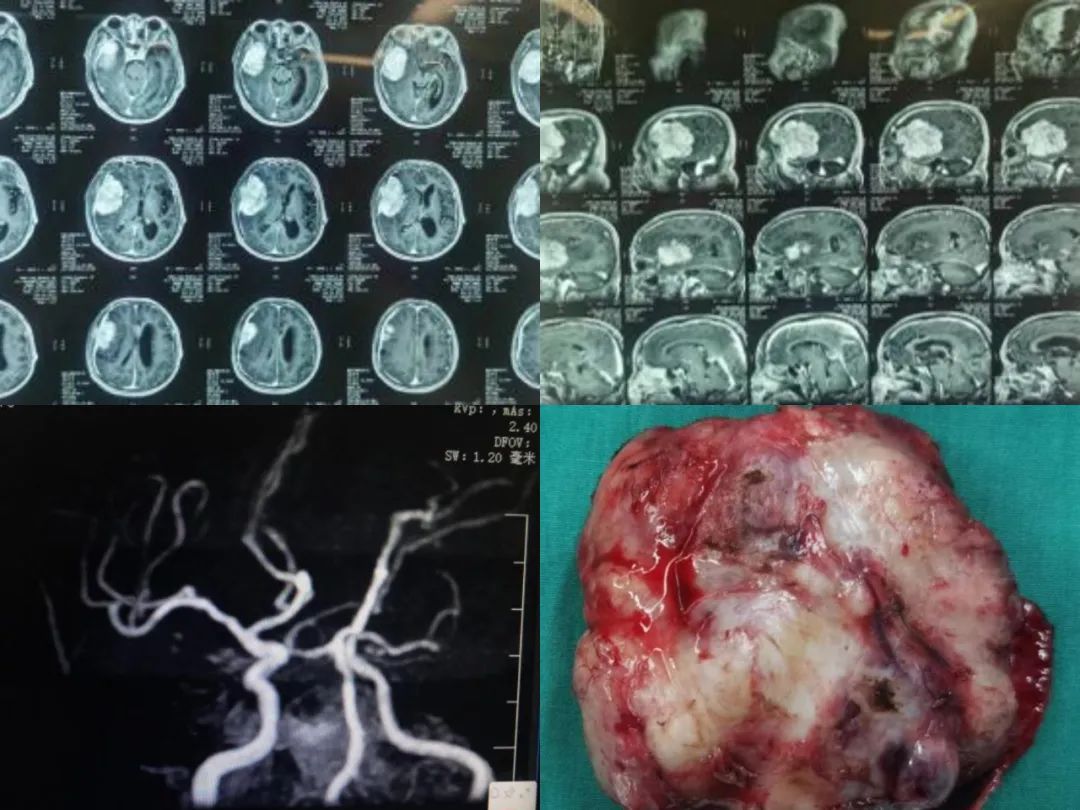

患者男性,76岁,以“右侧头部胀痛伴有记忆力下降”来我院就诊,头部增强核磁检查提示右侧额颞部巨大占位;同时MRA提示前交通动脉瘤,大小约为4mm×3mm;神经外科组织术前讨论,决定为其行脑膜瘤切除合并动脉瘤夹闭手术。术中肿瘤与脑组织粘连严重,较难分离,为此手术过程十分惊险,在医护团队的共同努力下,患者脑部肿瘤被完整切除,动脉瘤完美夹闭,大小约为44mm×66mm×63mm,术后病理回报为脑膜瘤。术后病人恢复良好,无神经功能障碍等并发症出现,成功帮助患者实现“两条腿”走路的愿望,现已安稳出院。术后复查恢复良好,患者向我院赠送锦旗表达感谢之情。

临床上颅内巨大脑膜瘤患者较少见,就像一颗定时炸弹,随时都有脑疝的风险,因此手术难度很大、风险很高,患者多在省级以上大医院救治,而该患者巨大脑膜瘤手术为我院神经外科独立完成。此次成功拆除“定时炸弹”,有我院DSA团队密切配合的努力,再次标志着我院神经外科团队在颅脑肿瘤治疗方面取得了质的飞跃。